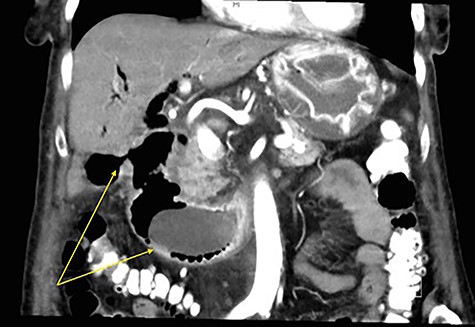

A 90-year-old female presented to the Emergency Department with right upper quadrant pain associated with nausea and persistent vomiting. She had been admitted seven months prior with acute necrotic cholecystitis, but given her advanced age, frailty, medical comorbidities and wishes to avoid surgery, she was managed with intravenous antibiotics and percutaneous cholecystostomy, which was removed eight weeks later. The patient was haemodynamically stable on presentation, but on examination had percussion tenderness in the right upper quadrant. Both abdominal X-ray and ultrasound demonstrated pneumobilia (Figs 1 and 2). A computed tomography (CT) of the abdomen showed a cholecystoduodenal fistula with a 60 × 30-mm gallstone in the third part of the duodenum causing gastric outlet obstruction (GOO), consistent with Bouveret syndrome (Fig. 3).

Coronal CT image of abdomen with arrows demonstrating a fistulous connection between the gallbladder and duodenum, and a large gallstone in the second part of the duodenum.